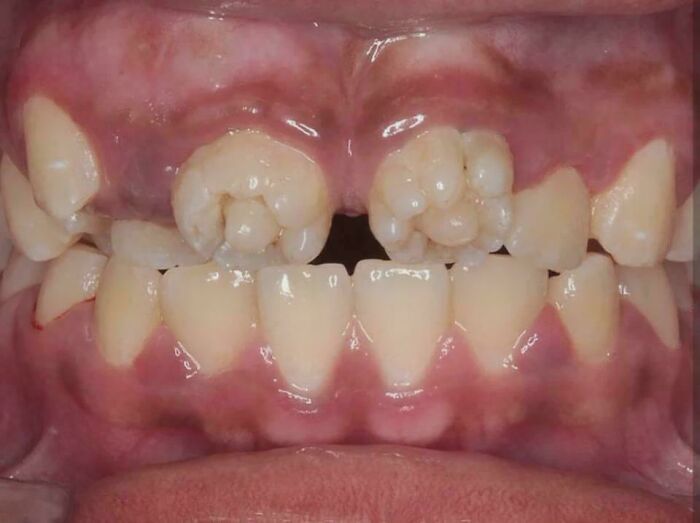

#16 These Are Mulberry Molars, Which Are Associated With Congenital Syphilis

Image credits: mriTecha